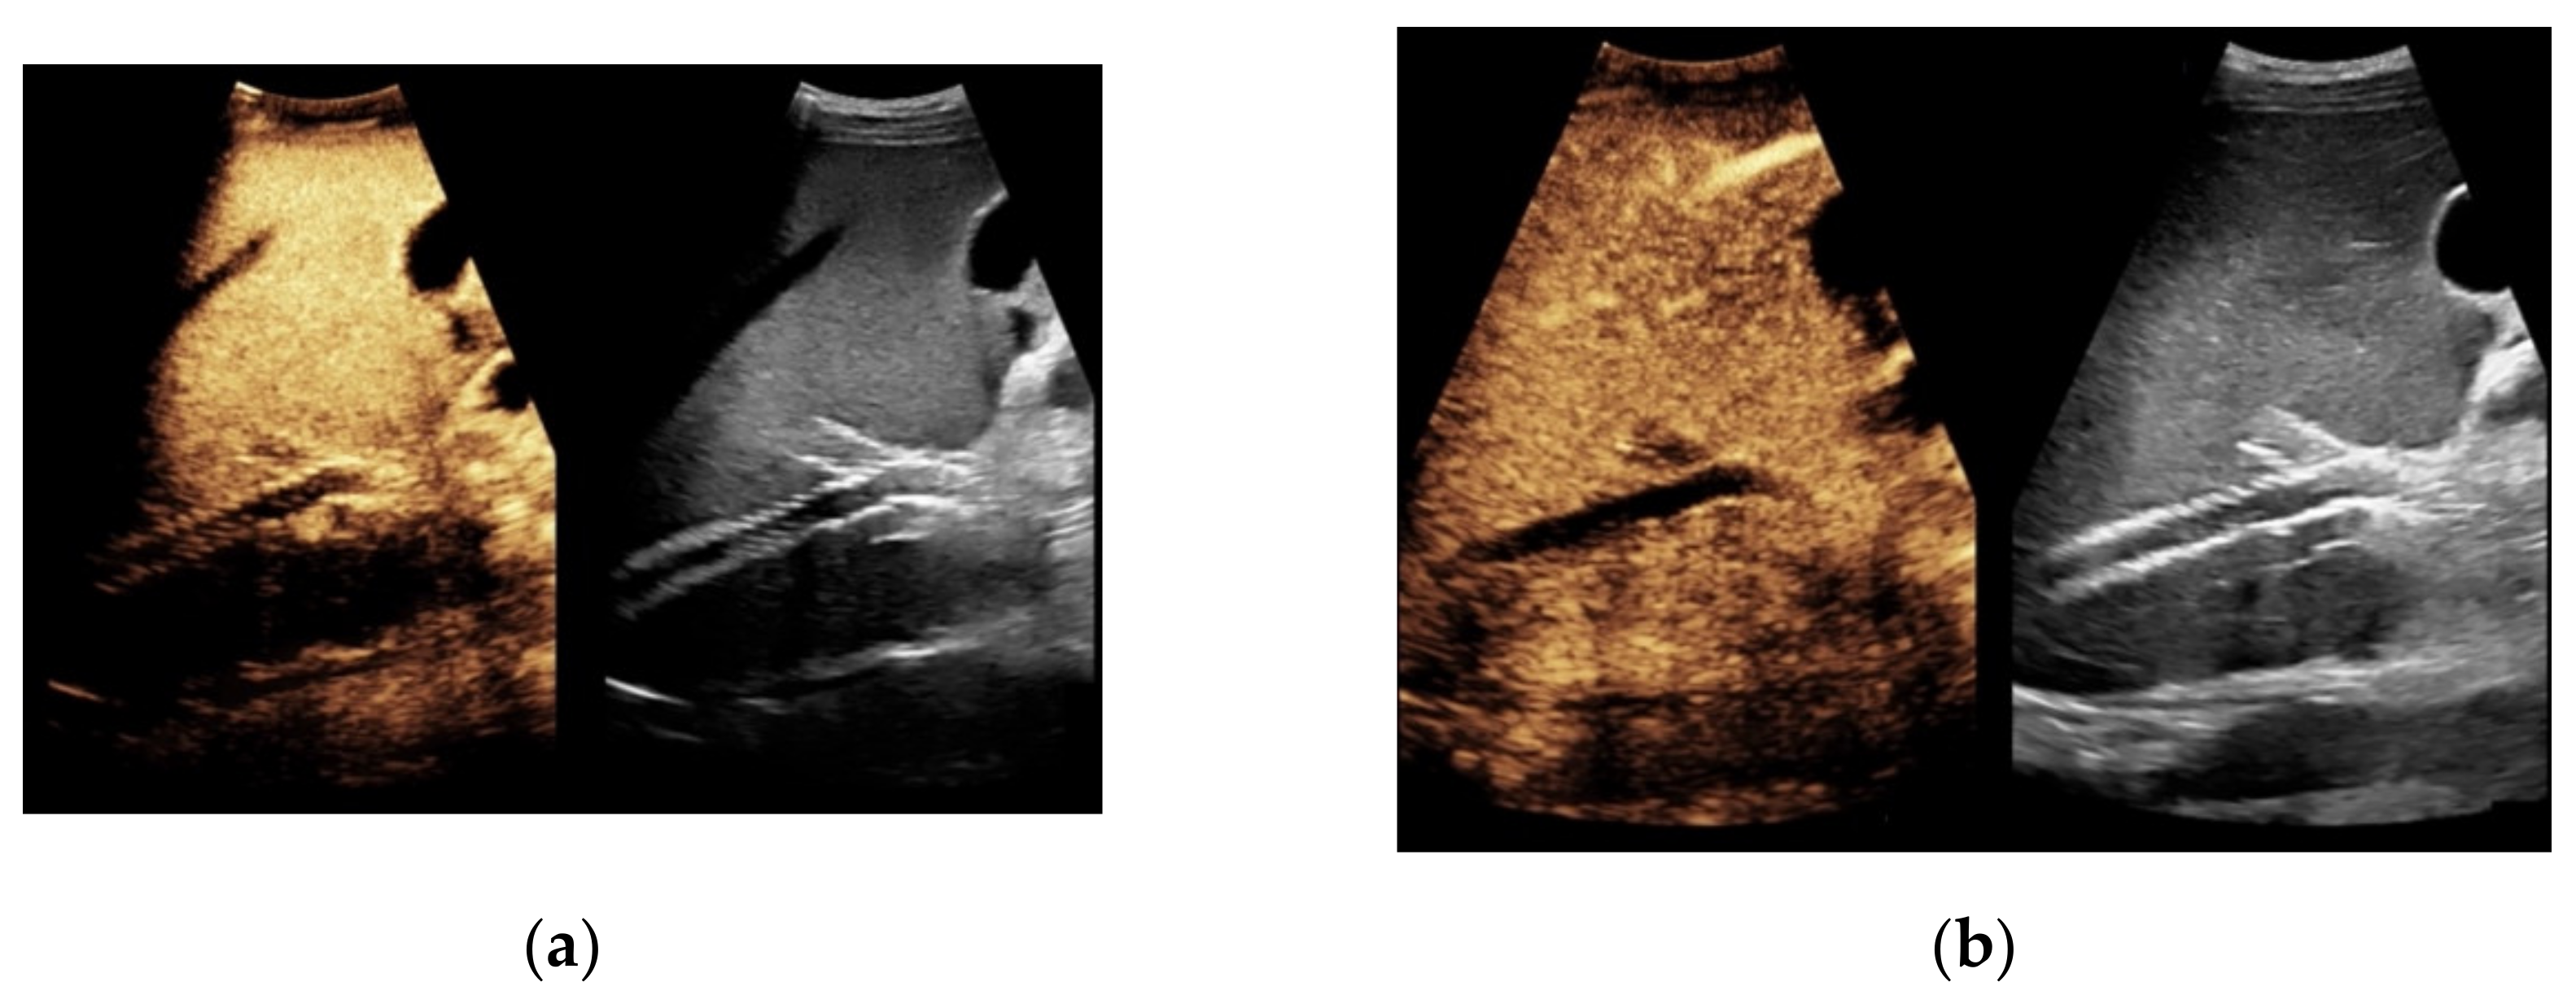

Figure 2. 57-year-old female patient with occluded transjugular intrahepatic portosystemic shunt in B-mode (a) and consecutive absent flow signal in Color Doppler ultrasound (b).